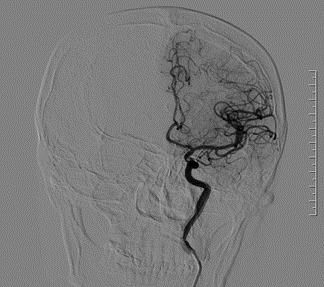

我院首例neuroform atlas支架应用于破裂的大脑中动脉宽颈动脉瘤.

neuroform atlas支架治疗颅内动脉瘤